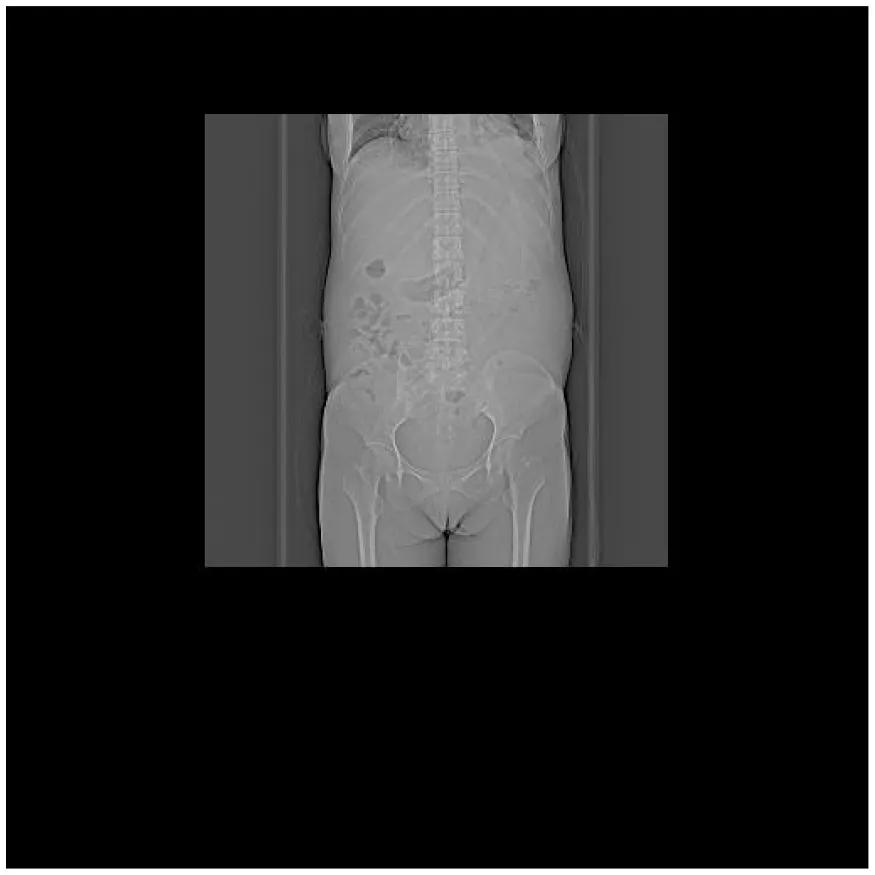

| (A) Abdominal CT at admission (7 February 2025) | (B) Abdominal CT after treatment (27 April 2025) |

|---|---|

CT images of the patient's abdomen.

A and B are abdominal CT scan images before and after autologous stem cell transplantation. A shows a significant amount of ascites, while B indicates a marked reduction in ascites. C, D, and E are PET/CT images before autologous stem cell transplantation, which show increased bone density in multiple areas, elevated FDG metabolism, no abnormal increase in CXCR4 expression; splenomegaly with diffusely increased CXCR4 expression and no abnormal FDG metabolism; and inflammatory changes in the peritoneum with scattered effusions in the abdomen and pelvis. F shows improvement after treatment.